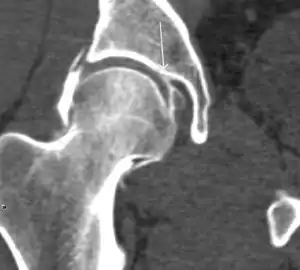

Most of the angles and measurements described in the plain radiograph section can be accurately reproduced on MRI. In addition, the superiority of MRI resolution with intra-articular contrast allows detection of labral and chondral abnormalities that may influence the choice of medical, percutaneous, or surgical management (Figure 9).[1]

Figure 9:

MR arthrography has proven superior in accuracy when compared to native MR imaging. It is considered the best technique to assess the labrum. Knowledge of the normal variable morphology of the labrum helps to differentiate tears from normal variants. A triangular shape is most commonly seen in 66% of asymptomatic volunteers, but round, flattened, and absent labra can also be found in asymptomatic populations. MR arthrography has demonstrated sensitivity over 90% and specificity close to 100% in detecting labral tears. Loose bodies are demonstrated as filling defects surrounded by the hyperintense gadolinium.[1]

Association between labral tears and chondral damage has been demonstrated. This underscores the interaction between cartilage and labrum damage in the progression of osteoarthritis. Chondral damage to the posteroinferior part of the acetabulum as a contrecoup lesion occurs in approximately one-third of pincer cases secondary to persistent abutment on the anterior part of the joint leading to a slight posteroinferior subluxation. This is considered a bad prognosis sign.[1]

MR arthrography can also demonstrate ligamentum teres rupture or capsular laxity, which are debated causes of microinstability of the hip. Elongation of the capsule or injury to the iliofemoral ligament or labrum may be secondary to microtrauma in athletes. MR can demonstrate abnormalities in these cases, such as increased joint volume or a ligamentum teres tear (Figure 9).[1]